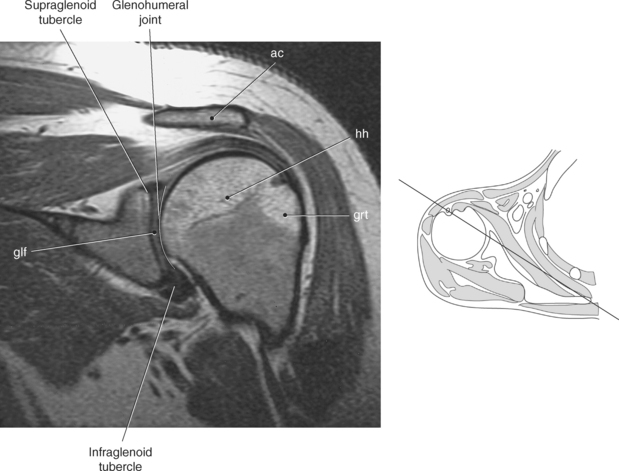

The scapula is a triangular-shaped flat bone that forms the posterior portion of the shoulder girdle. It has a medial margin, a lateral margin, and a superior margin. The margins are separated by the superior, inferior, and lateral angles (Figures 9.2 and 9.3). The anterior surface of the scapula, subscapular fossa, is flat and slightly concave. The posterior surface of the scapula is divided by the scapular spine into a smaller supraspinous fossa, and a larger infraspinous fossa (Figure 9.7). Four projections of the scapula provide attachment sites for the muscles and ligaments contributing to the shoulder girdle. These include the scapular spine, acromion, coracoid process, and glenoid process (Figures 9.7 through 9.10). The scapular spine arises from the upper third of the posterior surface of the scapula and extends obliquely and laterally to give rise to a flattened process termed the acromion. Located on the anterolateral surface of the scapula is a beaklike process termed the coracoid process, which arises just medial to the glenoid process and functions to protect the shoulder joint, which lies beneath it. The coracoid process is an attachment site for the pectoralis minor, short head of the biceps brachii, and the coracobrachialis muscles. The scapular notch is located just medial to the coracoid process, on the superior margin of the scapula and allows for the passage of the suprascapular nerve (Figure 9.2). The glenoid process, the largest of the projections, forms the lateral angle of the scapula and ends in a depression called the glenoid fossa (glenoid cavity) (Figures 9.7 through 9.9). There are two tubercles associated with the glenoid fossa, an upper supraglenoid tubercle and a lower infraglenoid tubercle, which serve as attachment sites for the biceps brachii and triceps brachii (Figure 9.8). The shallow articular surface of the glenoid fossa joins with the relatively large articular surface of the humeral head to create the freely moving glenohumeral joint (Figures 9.2, 9.3, 9.11, and 9.12).

Figure 9.10 Sagittal oblique, T1-weighted MR scan of shoulder.

Key: cor, Coracoid process; cl, clavicle; sup, supraspinatus; ac, acromion; inf, infraspinatus; de, deltoid; tm, teres minor; gl, glenoid; sub, subscapularis; h, humerus; grt, greater tubercle; sc, scapula; glf, glenoid fossa; hh, humeral head.